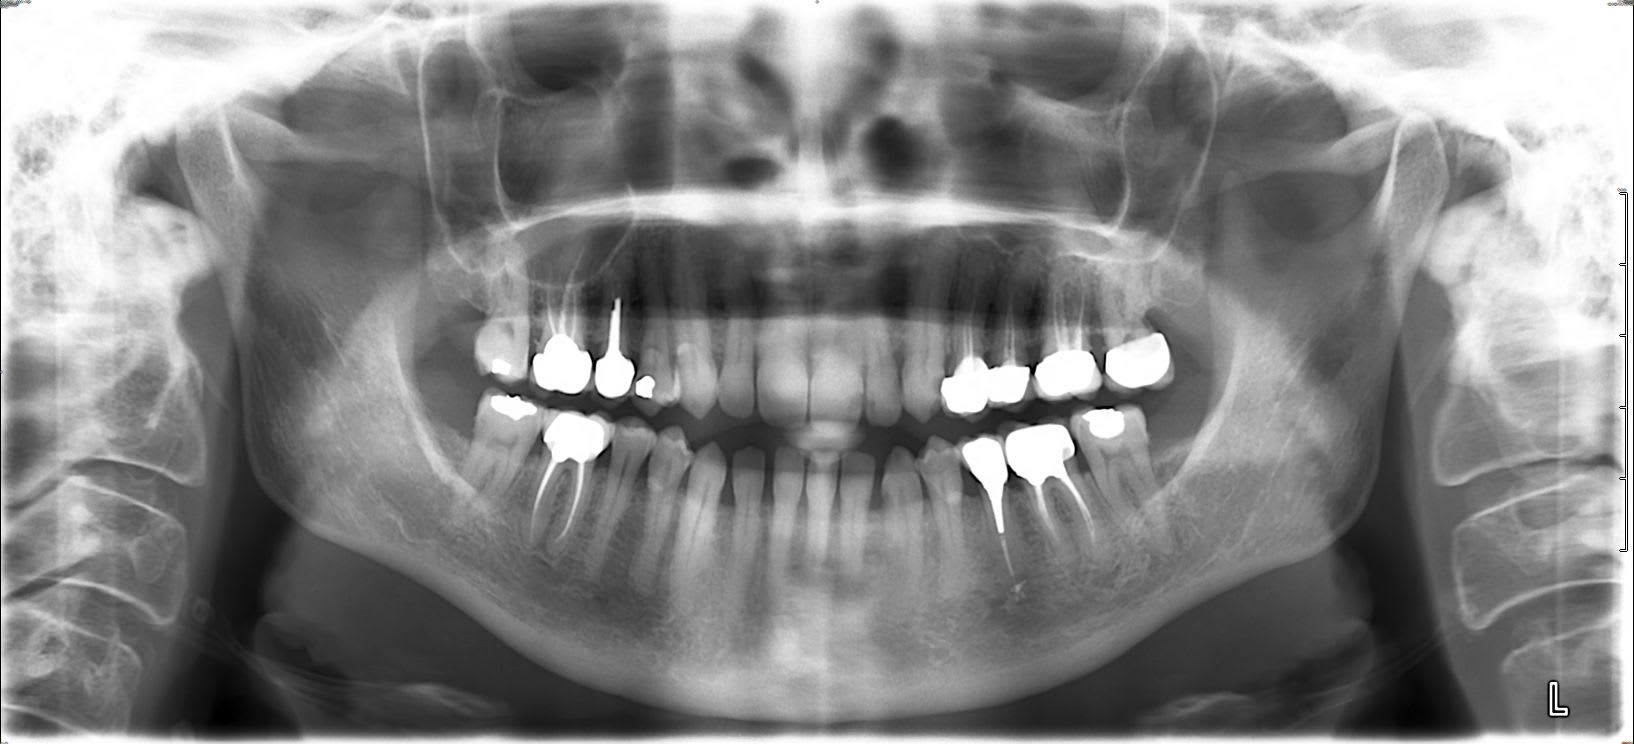

Recherches de foyers infectieux sur tendinites à répétition...

Que penser de l'angle mandibulaire droit et la zone péri apicale de 47 ( petit résiduel d'image de lipoe bien nette étendue aux 2 apex de 46 en 2014, RTE (pas de moi)...

Fais un cone beam ou à la rigueur des rétros, on voit rien sur ta pano

tu recherches un foyer infectieux dans ton cas de tendinite ? Pour ma part je regarderai plus du coté de la 14 et de la 23 pour un tel risque .

Belle pêche sous la 44 aussi non ?

hein??? non, tu as le trou mentonnier dans les parages....

mais c'est clair que la pano n'est pas top et pour une recherche plus fine, il vaut mieux compléter par des rétros.....

Je vois juste 21,28e d indus.

Que penser de la region periapicale de 47 ??

Bin faut faire les choses dans l ordre, un test au froid positif et de percussion negatif sont plus informatifs qu une pano... et dans le doute l examen radio complementaire c est la retro alveolaire 47.

le terrain est tres riche en foyers potentiels )

Désolée pour la qualité de la pano...

je transmets vos remarques au centre de radiologie qui devrait avoir les sous pour la qualité, vu qu'il en a trouvé depuis pour un cone-beam: mais bien sûr pas d'initiative pour le CB direct à suivre malgré mes "aiguillages " en ce sens, car honoraires sans doute réduits si fait le même jour... sans fixer pour autant de nouveau RV pour ce faire. J'attends de revoir la patiente pour des tests ciblés +- precription (Re) de cbct, mais c'est plus l'aspect de l'os plus largement que la zone apicale qui m'interpelle: empreinte de la sous maxillaire sur la table interne?

16,15,24,25,26 rapport étroit avec les sinus maxillaires (mais rechercher aussi s'il y a des signes locaux)... bon de toute façon les étios des tendinites c'est la bouteille à l'encre...